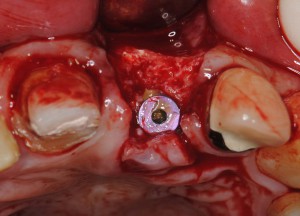

数カ月後、骨造成を確認したのちインプラント埋入。

数カ月後、骨造成を確認したのちインプラント埋入。